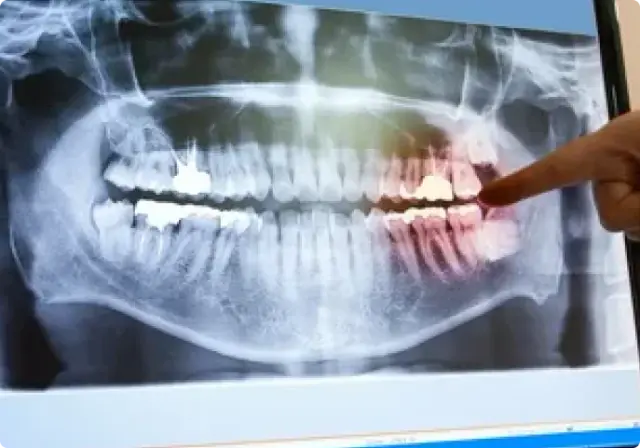

Digital X-ray photos

Complications and pain complaints cannot always be detected by the dentist. Sometimes the dentist needs more insight regarding the inner part of the tooth and/or gum. X-ray photo’s help to attain this information and helps tracking caries or tooth decay. We only work with digital x-ray equipment in order to reduce speed and to guarantee a low radiation dose. In some cases an overview of all teeth is necessary. In such a case panaroma X-ray photos are taken. In these photos the dentist has an overview of the teeth in whole.